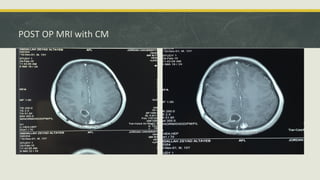

POST OP MRI with CM

POST OP MRIwith CM

• #40 These are axial T2 sequence cuts; which show a very small cystic cavity at the location of the excised cyst with a tract, a bit of edema some encephalomalacia within the adjacent brain parenchyma. no mass effect is found all the shifted structures were restored to their original position. Now regarding this cystic cavity, we presume that it’s a post-surgical change that is followed with this post op T1 with contrast images which show some peripheral enhancement which was not present initially.

• #41 This is a Post op T1 with contrast images which show very clear peripheral enhancement, vs the original lesion than only showed some focal enhancement, thus suggesting that this is a cystic cavity.